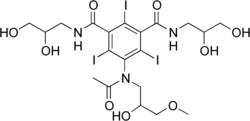

| Formula | C20H28I3N3O9 |

| Molar mass | 835.169 g·mol−1 |

Iopentol is an iodine-containing, water-soluble radiocontrast agent. The iodine atoms readily absorb X-rays, resulting in a higher contrast of X-ray images. It has a low osmolality, meaning that the solution has a relatively low concentration of molecules; this is usually associated with fewer adverse effects than high-osmolality contrast agents.[1][2]